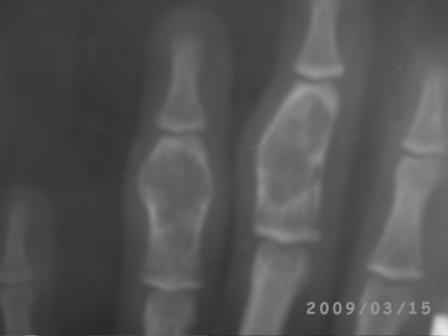

Конечно, мы во время операции будем брать материал на гистологию, а также удаление очага и замещение аутотрансплантатом тоже в плане рассматривается, как на примере, которая была представлена на форуме. правда снимки не очень качественные, прощу извинения!

Коллеги, почти уверен, что эти два случая поражения фаланг имеют различный генез. Простое выявление хрящевой ткани в биопсийном материале, увы, не дает еще диагноза.. Хотя местное лечение (если оно необходимо) может быть сходным. Единственное, не стал бы увлекаться широкими резекциями и массивными костными пластиками в детей.